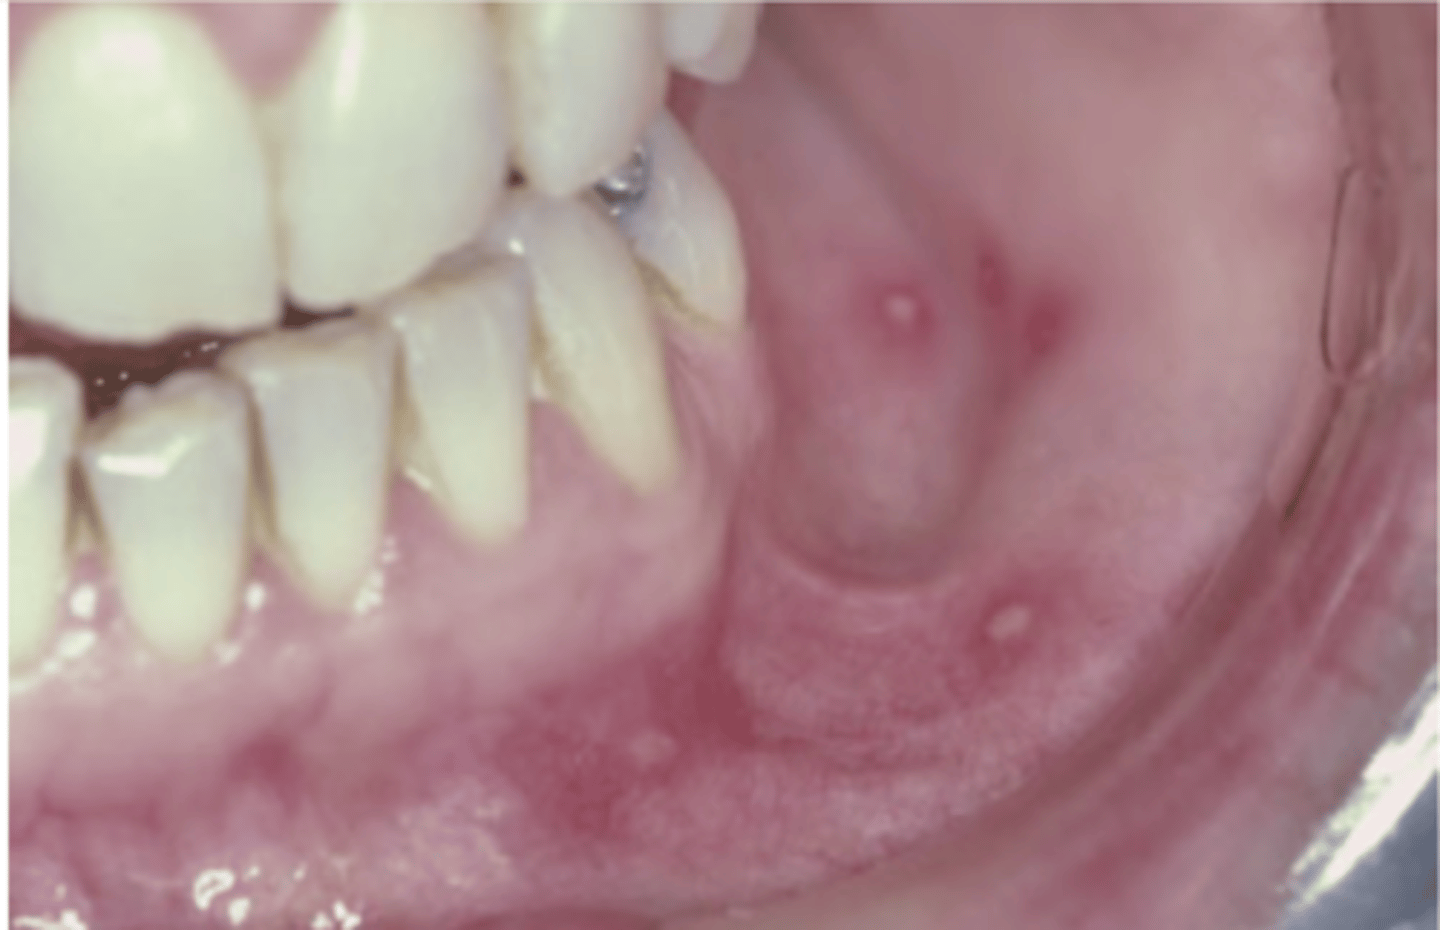

Condyloma Acuminatum

Hint: clustered, sessile, pink, well-demarcated exophytic mass with blunted surface projections